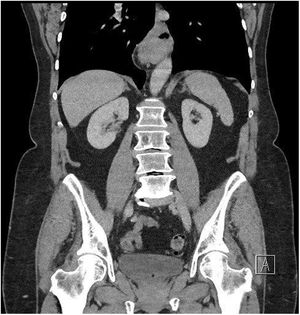

Caso clínicoSe trata de una paciente de 65 años diagnosticada de hernia de hiato sintomática de 2años de evolución. A pesar del tratamiento conservador, con recomendaciones posturales y dietéticas, y de inhibidores de la bomba de protones, la paciente presenta empeoramiento de la clínica de reflujo gastroesofágico. El control radiológico muestra incremento del tamaño de la hernia de hiato de 4cm (de 2cm a 6cm) (figs. 1-3). Preoperatoriamente se realiza una endoscopia que informa de gastritis y esofagitis en ausencia de esófago de Barret y lesiones neoplásicas. Ante el diagnóstico de hernia de hiato sintomática resistente al tratamiento y sospecha diagnóstica de esófago corto, se indica tratamiento quirúrgico.